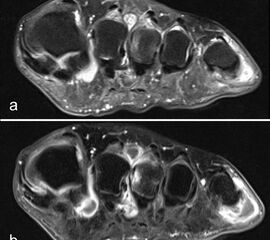

Der Begriff Morton-„Neurom“ ist im Grunde veraltet und irreführend, denn es handelt sich weder um einen Nerven- noch um einen Nervenscheidentumor, sondern um eine perineurale Fibrosierung. Da das interdigitale Gefäßnervenbündel charakteristisch in die Läsion hinein- und distal auch wieder aus der Läsion herauszieht, entsteht lediglich das Bild eines vom Nerven ausgehenden Tumors. Die charakteristischen Merkmale von Morton-„Neuromen“ sind deren Lage plantar auf Höhe der Metatarsaleköpfchen und die oft typische tropfenförmige Konfiguration (Abb. 10).

Aufgrund des hohen Bindegewebsanteils sind sie in der MRT in T2-gewichteten Bildern in der Regel auffallend signalarm, die T1 zeigt eine unspezifische Weichteilintensität. Die Anreicherung nach intravenöser Kontrastmittelgabe ist sehr variabel und erlaubt somit kaum diagnostische Rückschlüsse.

Durch seitliche Kompression des Fußes verlagern sich Morton-„Neurome“ oft weiter nach plantar in die Weichteile. Klinisch entspricht dies dem sogenannten Mulder-Zeichen 4. In der Bildgebung kann man sich den Effekt zu Nutzen machen, indem man in Bauchlage untersucht und durch die seitliche Fixierung eine entsprechende Kompression erzeugt. Die Befunde sind dann oft deutlich besser zu erkennen (Abb. 11).

Morton-„Neurome“ liegen fast immer im zweiten oder dritten Interdigitalraum. Zu beachten ist, dass Morton-„Neurome“ über lange Zeit größenkonstant sein können (Abb. 12) und kleinere Morton-„Neurome“ (unter 5 mm) sehr häufig bei asymptomatischen Gesunden beobachtet werden.